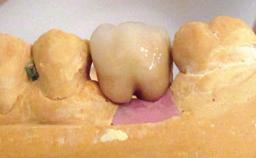

Prosthesis Type | FDP |

Retention | Cemented, with prosthesis margin < 3mm submucosal Cemented, with prosthesis margin < 3mm submucosal |

Provisional Implant-Supported Prosthesis | Prosthodontic margin < 3 mm apical to mucosal crest Prosthodontic margin < 3 mm apical to mucosal crest |